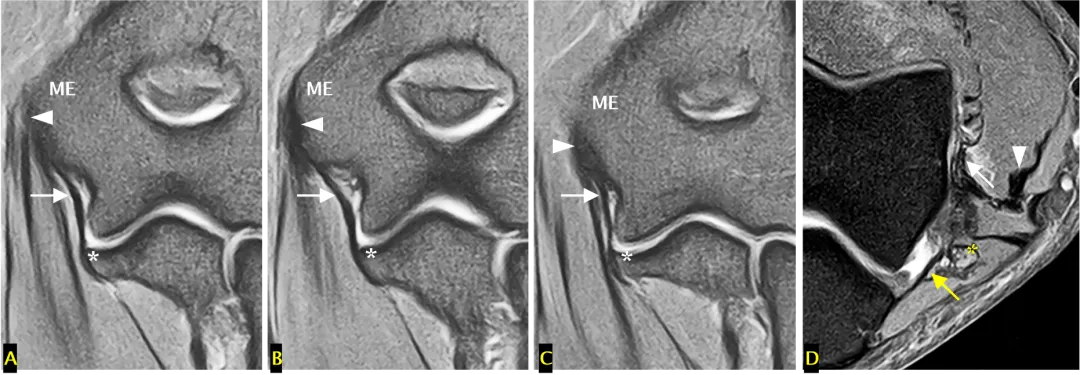

内侧副韧带复合体

内侧副韧带前束(白色箭头标注)从内上髁(ME 标注)下方延伸至尺骨冠突内侧的小结节(A-C中标注);内侧副韧带后束(D中黄色箭头标注)从内上髁后方延伸至鹰嘴,构成尺神经沟的底部;可见共同屈肌肌腱(箭头头标注)和尺神经(D 中标注)。